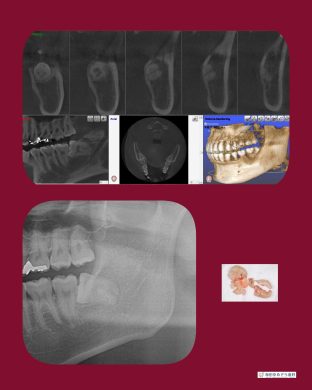

横向き親知らずの抜歯症例

院長はこのような横向きに埋まっている抜歯ケースも

1000症例以上の手術実績あり☆

横に埋まっている場合はCT撮影で安心です☆